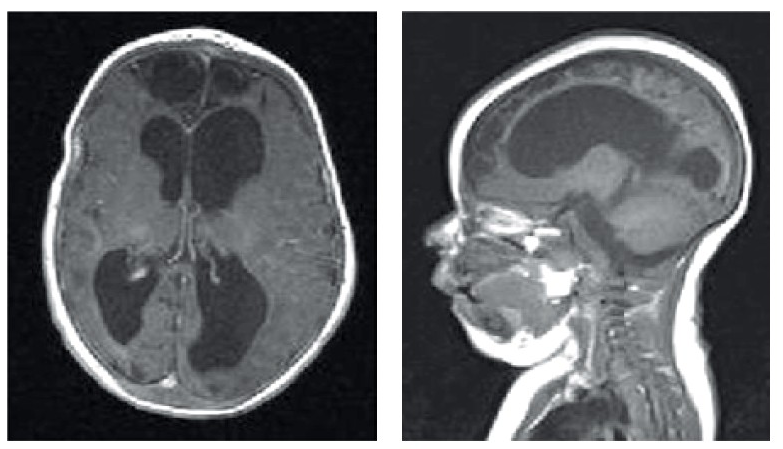

Meningitis

Es una enfermedad infecciosa que ataca las meninges del cerebro y la médula espinal.

Esta, es producida mas comúnmente por bacterias como el neumococo, meningococo, hemofilo y listeria que llegan al cerebro por el torrente sanguíneo o a través de alguna infección en el oído o senos paranasales. También puede contagiarse de manera viral o fungica.

La meningitis es una enfermedad de cuidado, ya que se presenta como una simple gripe con síntomas comunes, pero puede ser potencialmente mortal. También puede dejar secuelas en aquellos que la superan, como: perdida de la audición, perdida de la memoria, impedimentos en el aprendizaje, daño cerebral y psicomotor, convulsiones, insuficiencia renal, entre otros.